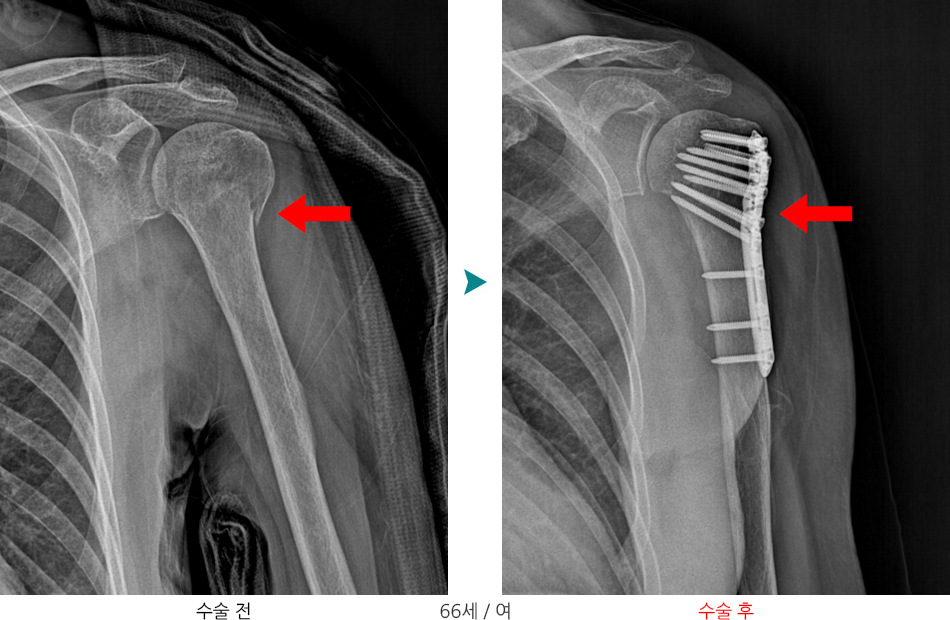

상완골 근위부 골절은 상완골(위팔뼈)의 머리 부분(견관절 가까이)에 생기는 골절입니다.

X-ray & CT : 골절 형태 및 전위 정도 평가

변위가 크거나 관절면을 침범한 골절의 경우

- 개방적 정복술 및 금속판/금속나사를 이용한 내고정술 시행